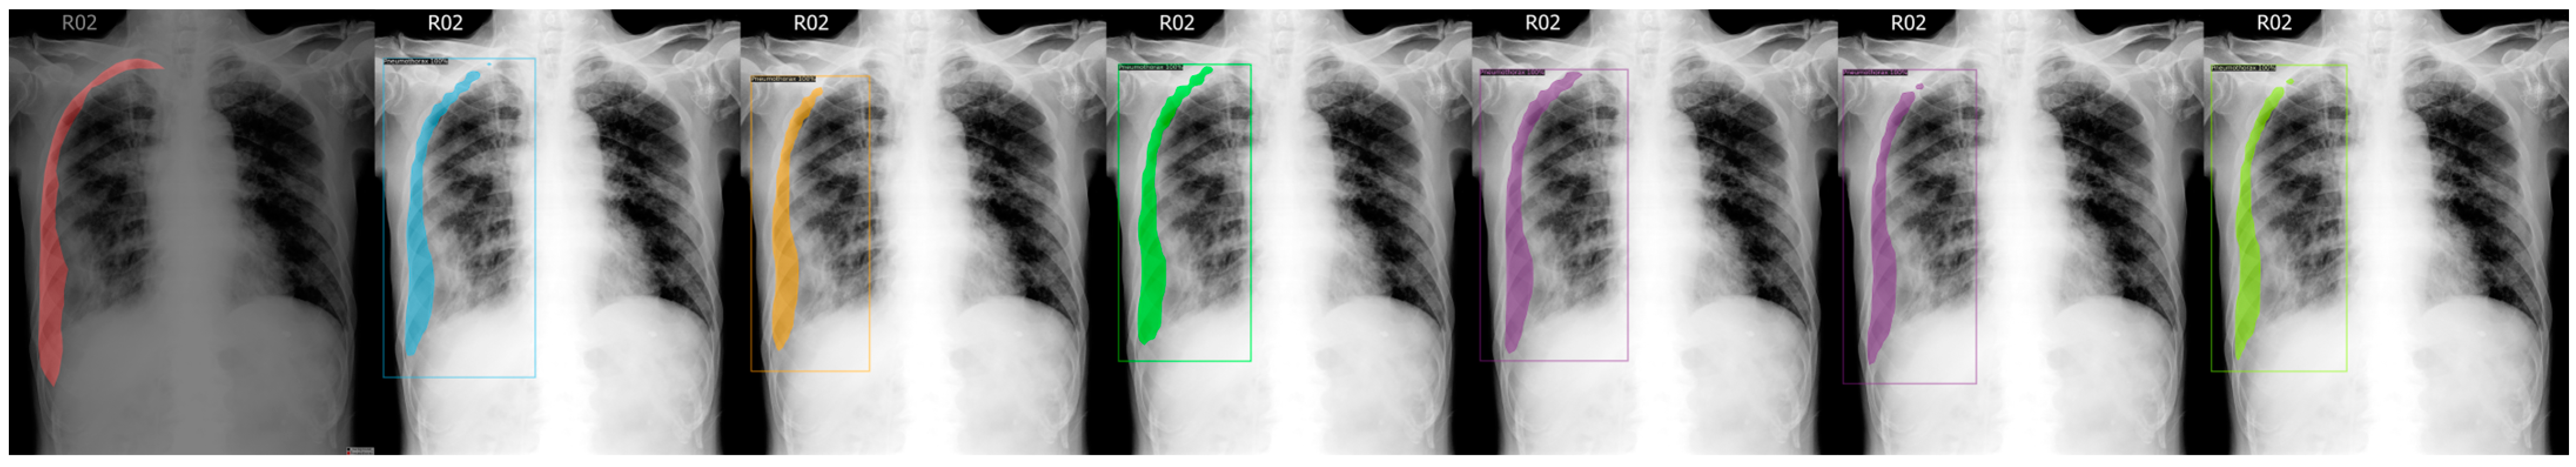

Below are the output results for the test images set, from Figure 3, Figure 4, Figure 5, Figure 6 and Figure 7, which are not in the training or validation set used for training the models.

Figure 3.

From left to right: Ground Truth, ResNet50 (COCO), ResNet101 (COCO), ResNeXt101 (COCO), ResNet50 (LVIS), ResNet101 (LVIS), and ResNeXt101 (LVIS). This patient had pneumothorax in their right chest.

We chose a few examples to demonstrate the capabilities of various models. These images consisted of X-ray images of pneumothorax patients with different areas of disease inflicted. The inclusion of multiple positions and areas in the figures lets us observe the possible outcomes and the differences between the models. In Figure 3 and Figure 6, the patients had pneumothorax on the right side of their chest, with the patient in Figure 6 only affecting the top part, while the patient in Figure 3 had pneumothorax on the outside wall of their right lung. In Figure 4, Figure 5 and Figure 7, the patients had pneumothorax in the left side of their chest, while the patients in Figure 4 and Figure 5 had the upper part of their left lung mostly collapsed, indicating a serious issue of pneumothorax disease. In Figure 5, there are cavity areas at the bottom part, too. In the same image, the ground truth included a portion protruding below the area of the top detection portion due to the late-stage pneumothorax with most of the upper part of the lung collapsing, and all models were unable to detect the cavity of the protruded part. In Figure 7, the patient is seen with a fixation, with the pneumothorax affecting the top left lung, albeit with a smaller area.